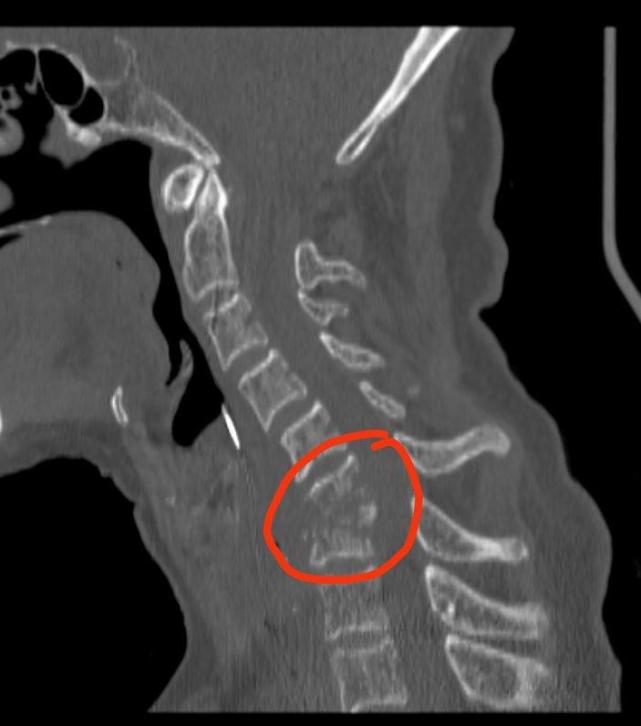

一根鸡骨头卡喉咙 竟让她差点瘫痪

小小一根鸡骨头卡喉咙,竟让她差点瘫痪